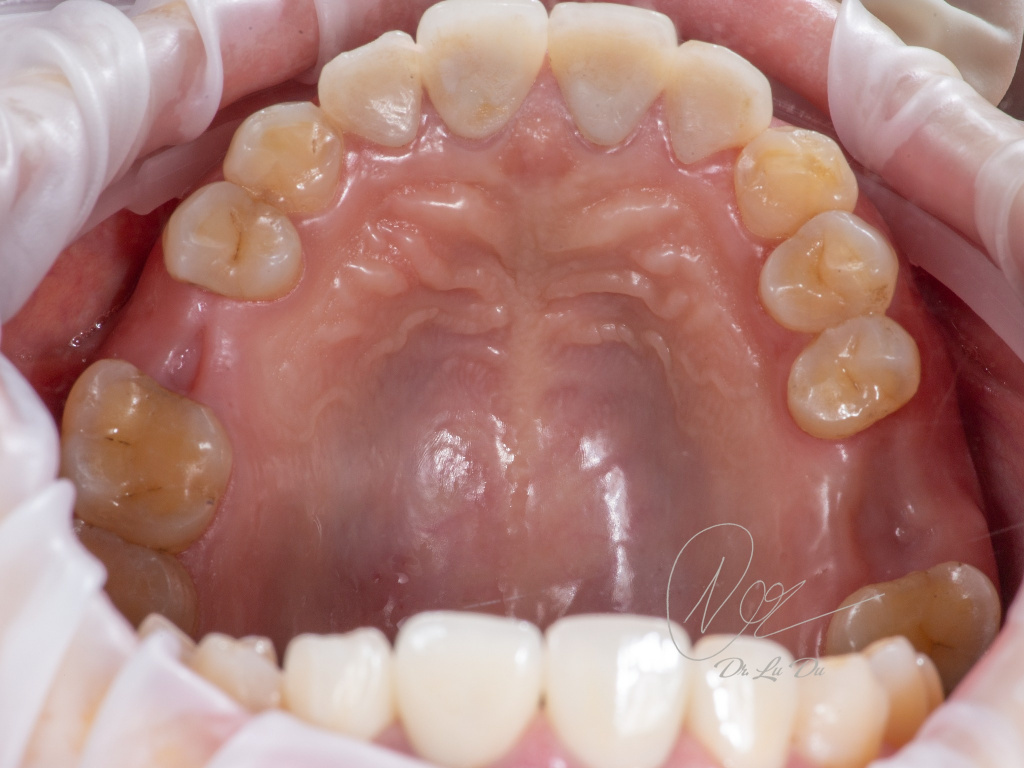

Имплантация AnyRidge с двусторонним закрытым синус-лифтингом.